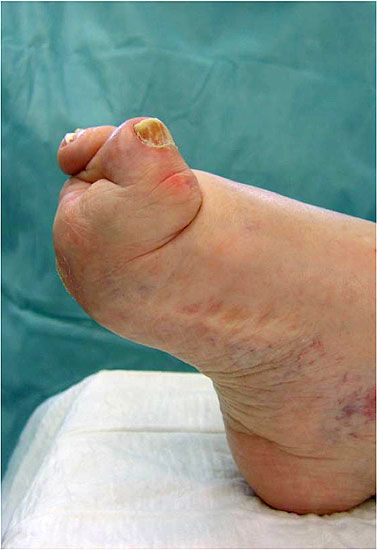

• Vorfuß in fixierter Plantarflexion des ersten Strahls (medialer Hohlfuß, Ballenhohlfuß, Pes cavovarus) (Abb.1 und 2)

Zum Lesen der Bildbeschreibung und zur Vollansicht bitte die Bilder anklicken. Bilder: A. Simon